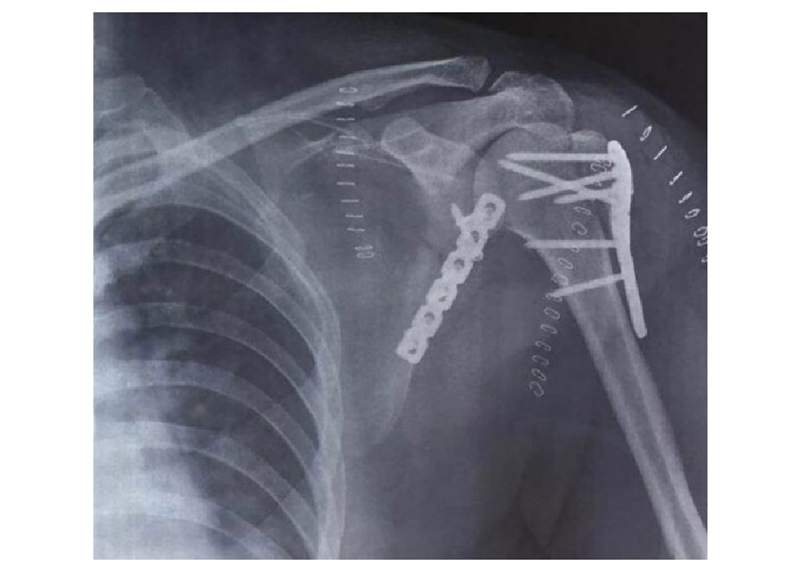

本例患者在术中对肩胛骨体部骨折块采用缝线辅助固定技术,将高强度缝线穿过骨折线两侧预钻孔后,以Nice结进行固定。肱骨近端及肩胛颈内下方骨折采用接骨板固定(图24)。

术后X线显示接骨板位置良好,实现肩胛骨骨折解剖复位(图25)。

图25 X线示肱骨近端及肩胛骨内固定位置良好,骨折复位满意